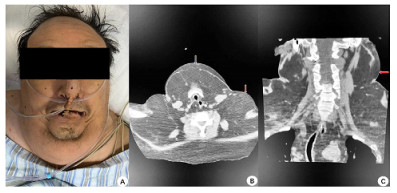

入院查体:患者呈昏迷状,双侧瞳孔等大等圆,直径3 mm,对光反射迟钝,颈部(图 1)和肩部(图 2)分别可见7 cm×4 cm及5 cm×6 cm大小软组织肿胀,质软,腹部及双侧大腿内侧(图 3)可见5 cm×6 cm软组织肿胀,质软,双肺呼吸音粗,双肺可闻及少许湿啰音,心律齐,各瓣膜听诊区未闻及病理性杂音,腹部膨隆,腹部查体不配合。入院后相关检查见表 1,腹部超声提示脂肪肝,心脏超声示左室壁运动弥漫性减低、左室壁肥厚,左室射血分数47%。

| A:患者下颌及颈部脂肪隆起;B:颈部CT平扫(轴位-下颌及颈部皮下脂肪影增多);C:颈部CT平扫(冠状位-颈部皮下脂肪影增多) 图 1 患者下颌及颈部病变(红色箭头所示) |

| A:患者枕部、肩部、背部脂肪隆起;B:颈部CT平扫(轴位-枕部皮下脂肪影增多);C:颈部CT平扫(冠状位-肩部皮下脂肪影增多) 图 2 患者枕部、肩部及背部病变(红色箭头所示) |